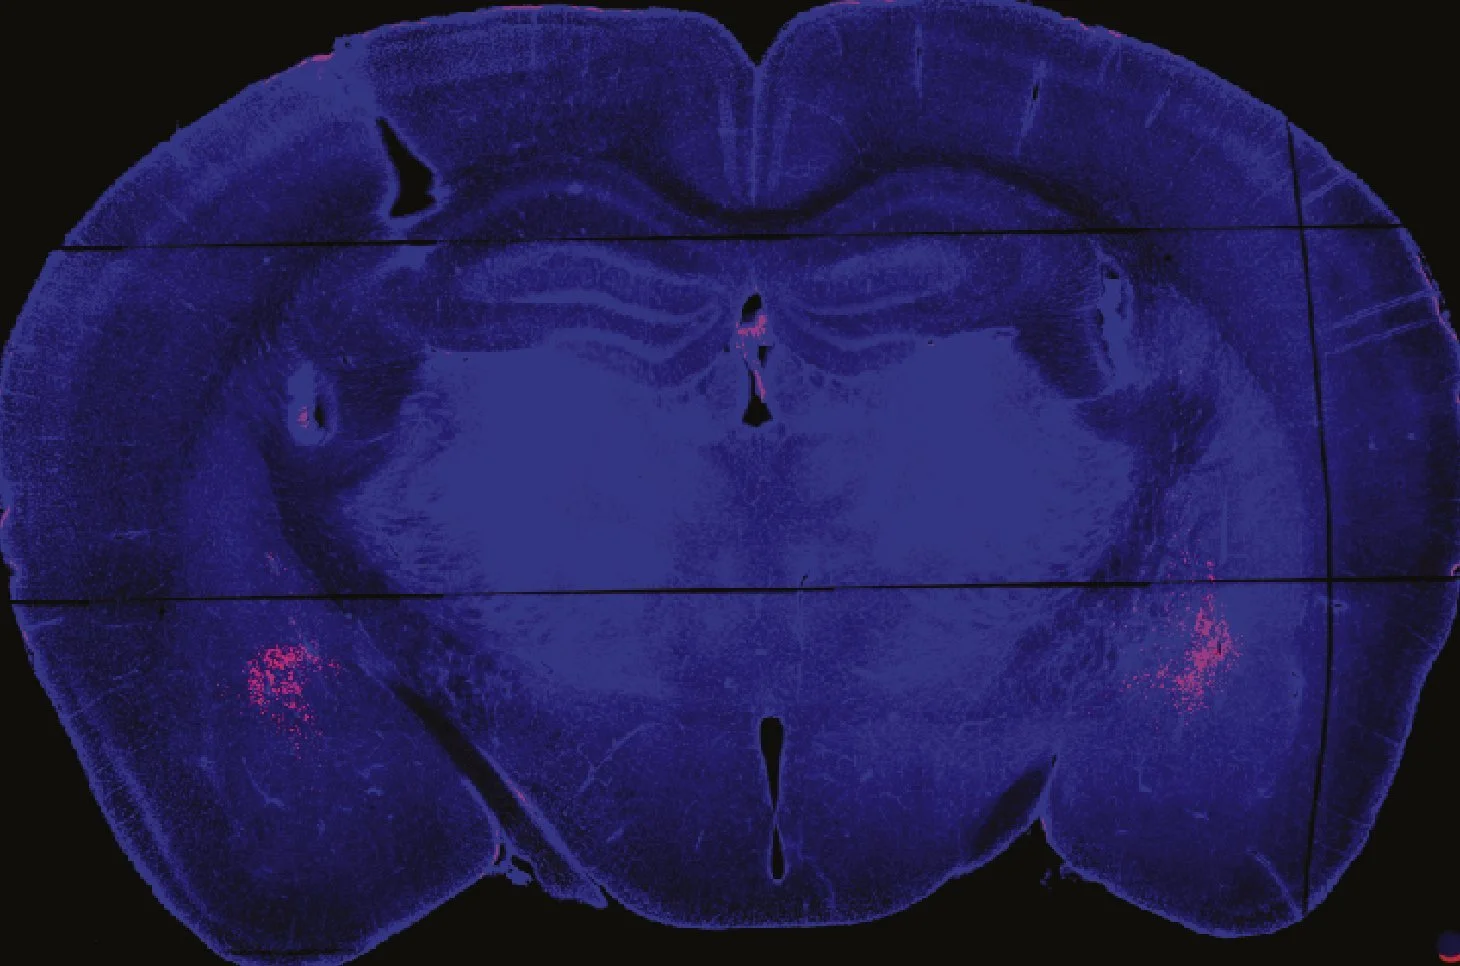

The process begins in the ventral tegmental area (VTA), where dopamine-producing neurons are activated. They release dopamine and send it to the nucleus accumbens (NAc), the brain’s reward center.

A recent study from his lab offers hope in this regard. They found that two different brain regions are involved in fentanyl addiction. When fentanyl is consumed, one experiences euphoria, which provides positive reinforcement, encouraging repeated use of the drug. When not consumed, the addict experiences fear and other withdrawal symptoms, known as negative reinforcement, which drives the person to seek the drug.

Previously, researchers believed that both positive and negative processes originate from a single brain region, and designed treatments like methadone to target it. The new findings suggest that µ-opioid receptors in VTA drive reward, while withdrawal stems from those in the central amygdala (CeA). This separation reveals that addiction indeed involves two independent brain pathways, opening possibilities for more targeted and effective treatments.